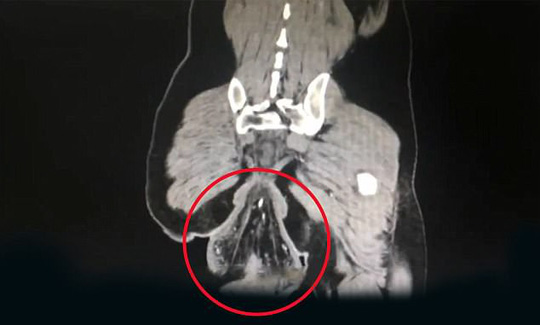

12/02/2018 14:57Mê chơi game đến mức ruột già 'tụt' ra ngoài

Theo trang Daily Mail, vụ việc nói trên xảy ra vào ngày 4-2 ở TP Trung Sơn, tỉnh Quảng Đông - Trung Quốc.

Các bác sĩ cho biết phần dị vật có hình dạng khối u này chính là trực tràng đã mất sự gắn kết với cơ thể nhưng vẫn còn bám vào hậu môn.

Các bác sĩ gọi tình trạng này là chấn thương trực tràng bị gây ra do người đàn ông ngồi hơn 30 phút trong nhà vệ sinh. Chấn thương trực tràng là trường hợp phần cuối của ruột già mất sự gắn kết với cơ thể và có thể được nhìn thấy lòi ra bên ngoài hậu môn.

Bệnh nhân này cũng thừa nhận mình chơi game trên điện thoại di động khi đang đi vệ sinh.

Bác sĩ Su Dan, người làm việc tại khoa phẫu thuật dạ dày – ruột của bênh viện thuộc Trường ĐH Sun Yat Sen, cho biết tình trạng của người đàn ông không được tiết lộ danh tính này khá nghiêm trọng.

Bác sĩ Su cho hay: "Bệnh nhân bị sa trực tràng từ khi lên 4 tuổi nhưng phần trực tràng lòi ra ngoài có thể tự thu lại. Tuy nhiên, bệnh nhân đã không đủ điều kiện để điều trị khi đó nên khiến tình trạng trở nên tồi tệ hơn".

Hình ảnh chụp cắt lớp vi tính (CT) cho thấy phần ruột lòi ra ngoài hậu môn có hình quả bóng với đường kính 16 cm.

Theo bác sĩ Su, bệnh sa trực tràng thường xảy ra ở trẻ em hoặc người cao tuổi. Đối với một số trẻ nhỏ, tình trạng có thể liên quan đến rối loạn chức năng bẩm sinh.

Mặc dù bệnh nhân mắc phải tình trạng này từ khi còn rất nhỏ nhưng nguyên nhân dẫn đến sự cố khiến phải nhập viện là thời gian đi vệ sinh quá lâu. Bác sĩ Su cho rằng bệnh nhân cố đi vệ sinh và hành động này có thể đã làm suy yếu các cơ xương chậu. Ca phẫu thuật loại bỏ phần ruột già lòi ra ngoài thành công và người đàn ông này đang dần hồi phục.

Bác sĩ Lv, một đồng nghiệp của bác sĩ Su, giải thích dù ngồi bệt hay ngồi xổm trên bồn cầu, áp lực khoang bụng sẽ tăng lên và buộc ruột già lòi ra ngoài vì cơ xương chậu không đủ lực giữ lại. Tiến sĩ Lv khuyến cáo bất kỳ ai mắc phải tình trạng tương tự thì nên điều trị càng sớm càng tốt.